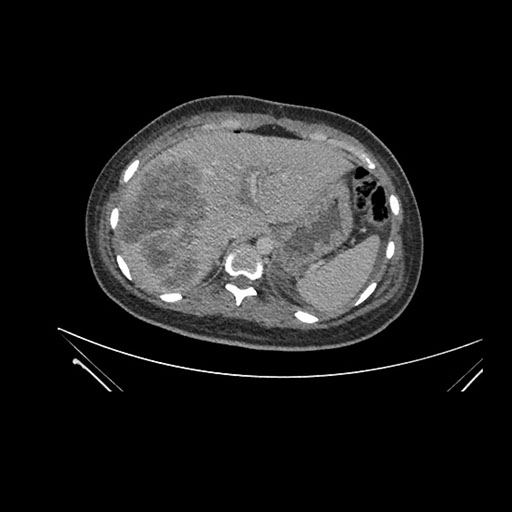

Coronal Venous

Imaging analysis

Based on initial findings, which issue(s) would you be most concerned about?